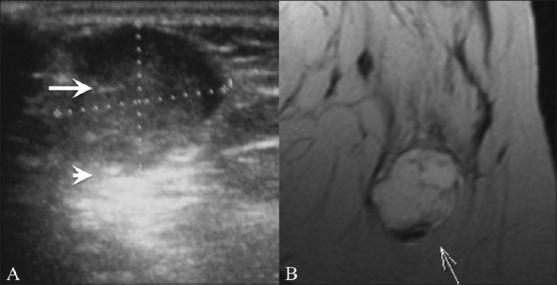

USG of the breast is now an established modality. It is used in the characterisation of focal breast lesions as well as in the primary evaluation of mammographically dense breasts. It helps guide biopsies as well. We present a pictorial essay on the role of USG in various breast pathologies.